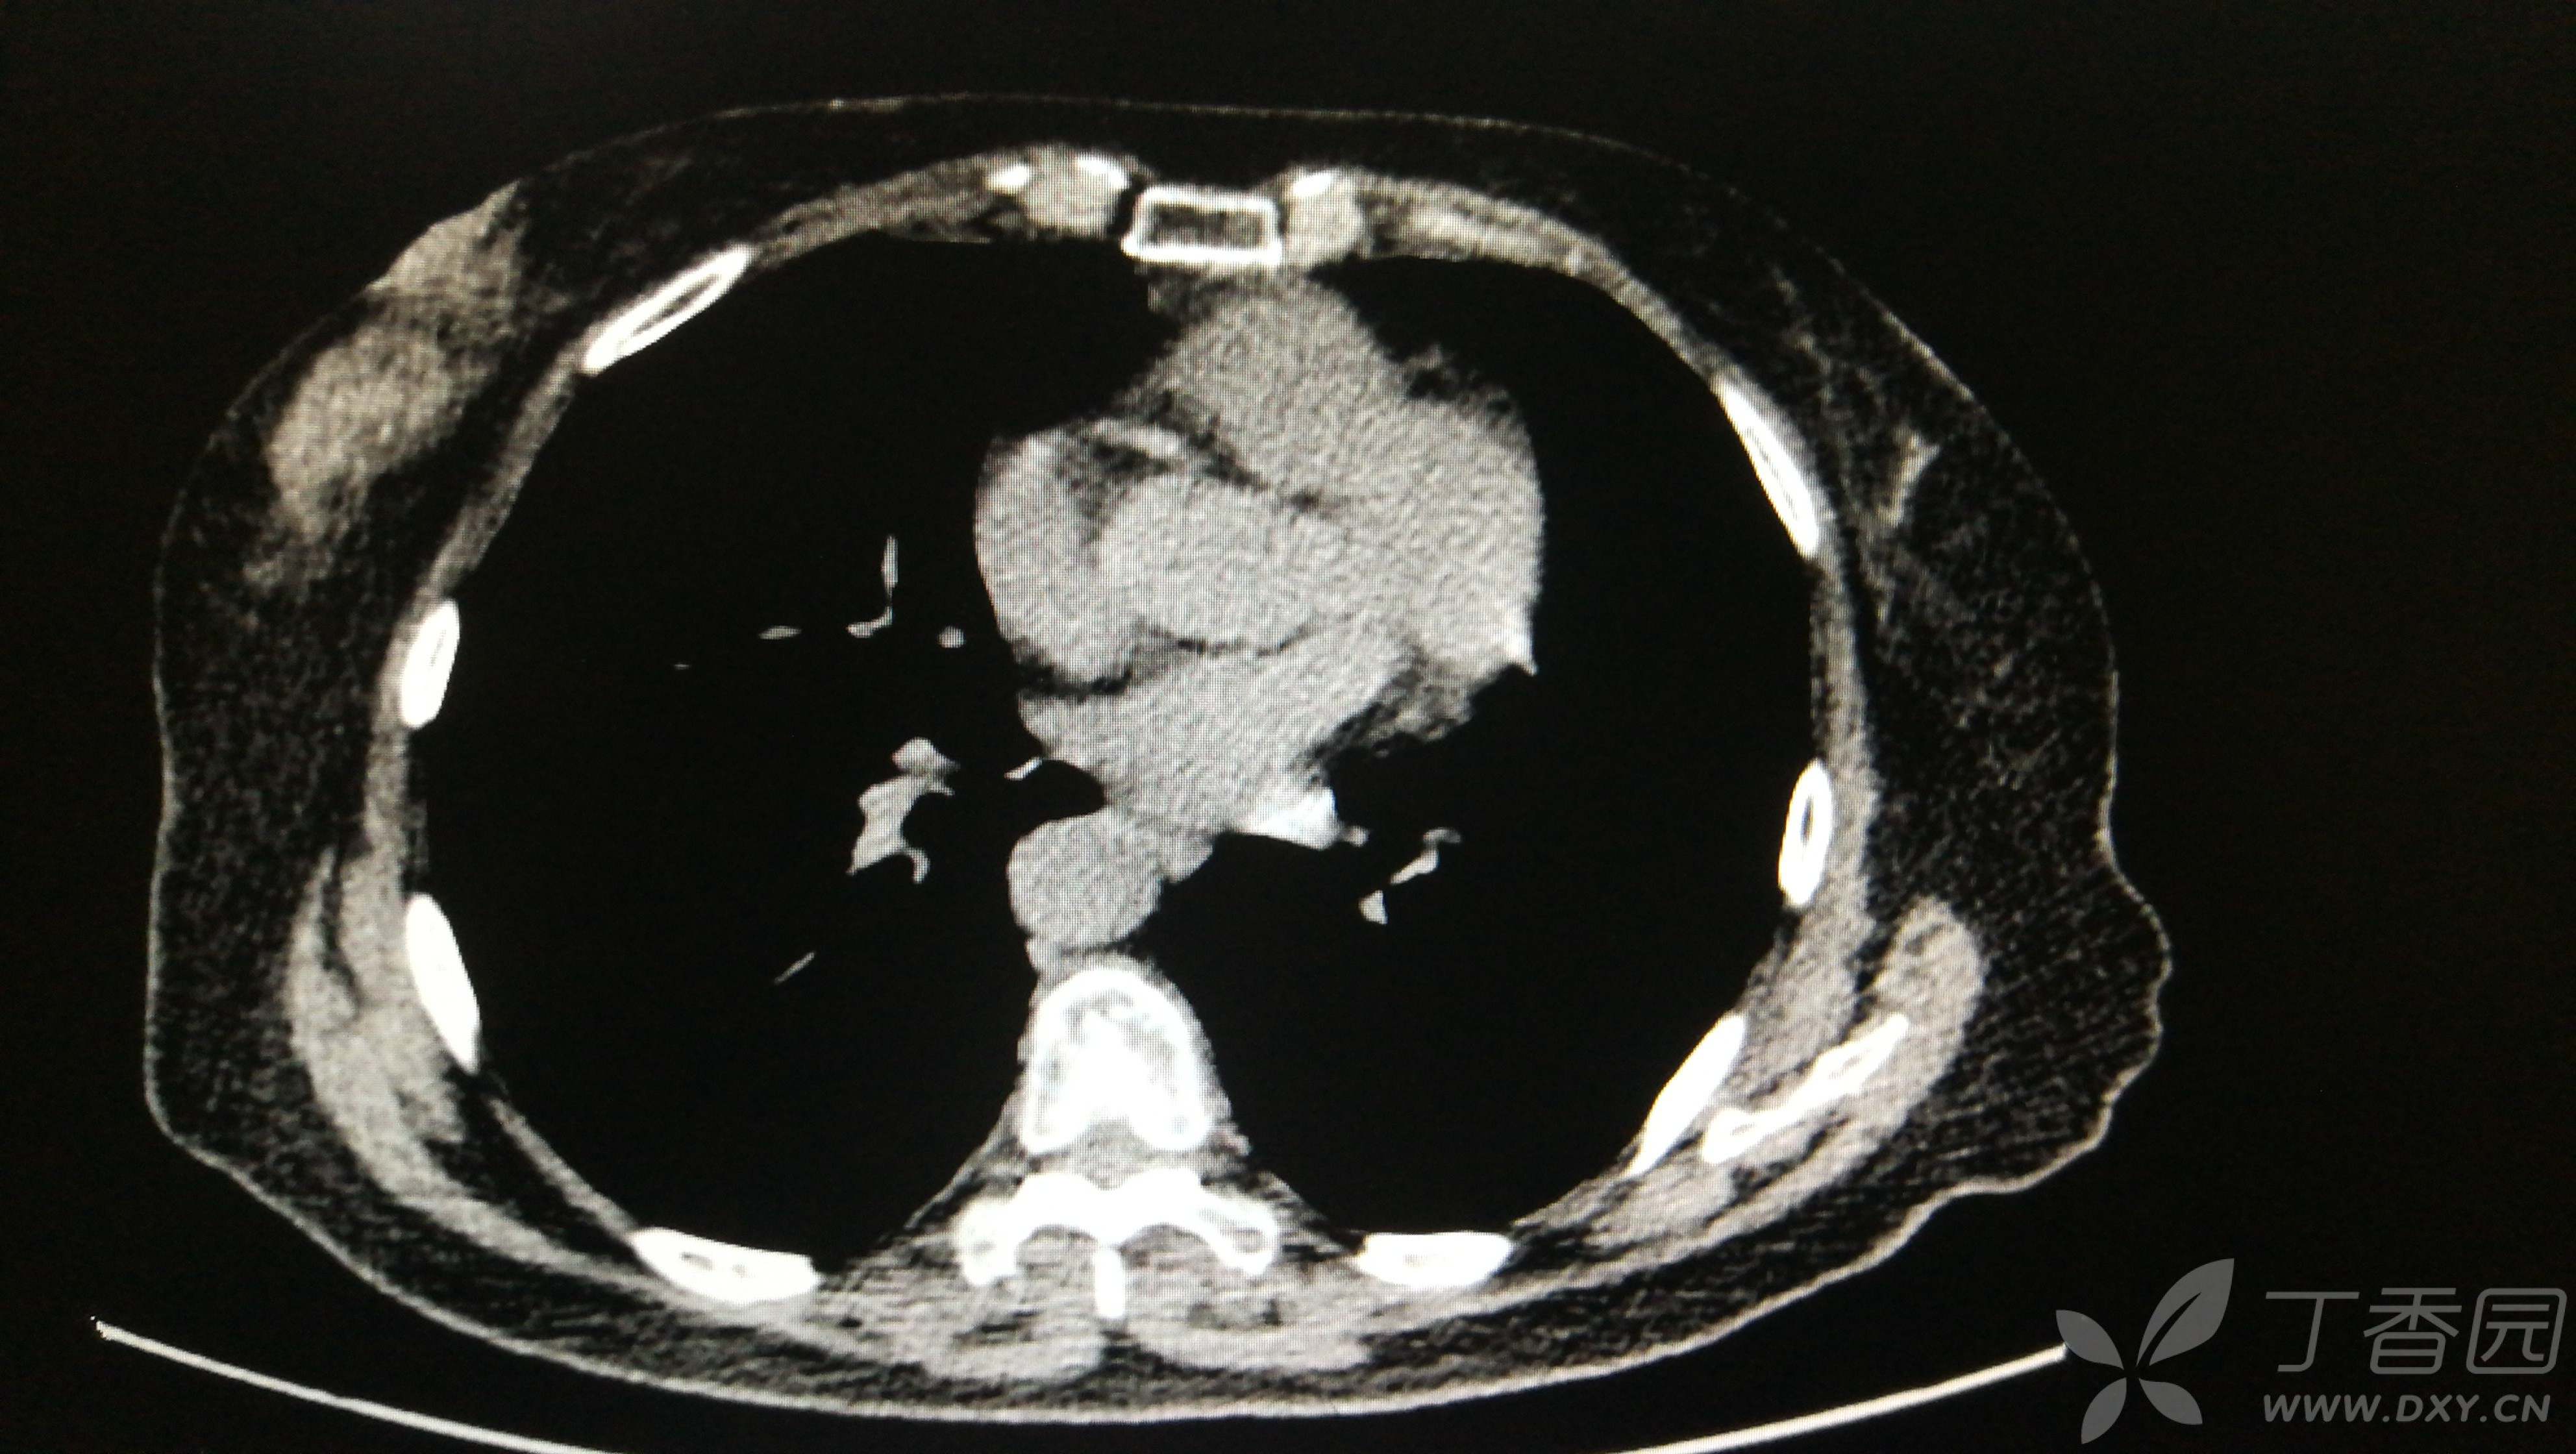

简要病史:查体发现双肺多发结节一个月。

辅助检查:胸部平扫CT

①双肺多发磨玻璃结节

②右下肺实性结节